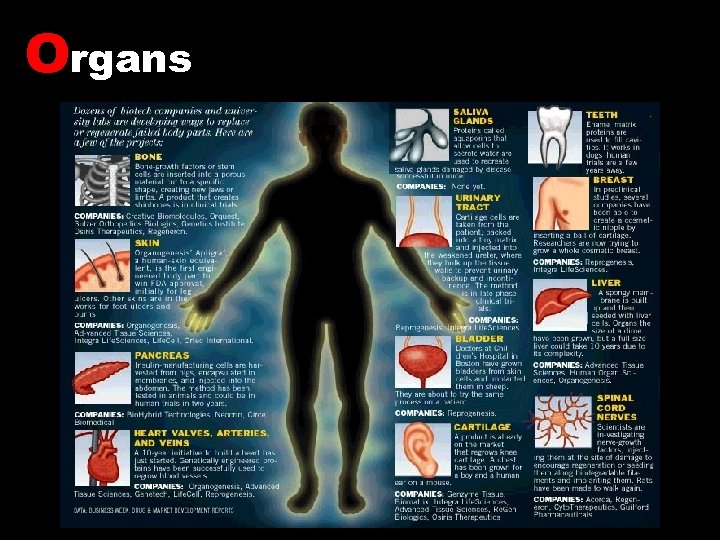

Organs

Organs

Commercial Products Neo-bladder – a commercial synthetic bladder A surgeon takes a small, full-thickness biopsy from the patient’s bladder. urothelial and smooth muscle cells that are capable of regeneration are isolated. The isolated cells are cultured separately until there a sufficient quantity. The cultured cells are properly seeded onto a biodegradable scaffold shaped like a bladder. The biodegradable scaffold dissolves and is eliminated from the body, leaving a functioning bladder made only of the patient’s own newly regenerated tissue. The body uses the neo-bladder construct to regenerate and integrate new tissue, restoring the bladder’s functionality. The neo-bladder construct is implanted by the surgeon using standard surgical techniques. Quality assurance that the cells attach and grow properly throughout the scaffold. After about 8 weeks, the neo-bladder construct is returned to the surgeon for implantation. Tegion, Courtesy of Tengion East Norrington, PA 2007.

Commercial Products Neo-bladder – a commercial synthetic bladder A surgeon takes a small, full-thickness biopsy from the patient’s bladder. urothelial and smooth muscle cells that are capable of regeneration are isolated. The isolated cells are cultured separately until there a sufficient quantity. The cultured cells are properly seeded onto a biodegradable scaffold shaped like a bladder. The biodegradable scaffold dissolves and is eliminated from the body, leaving a functioning bladder made only of the patient’s own newly regenerated tissue. The body uses the neo-bladder construct to regenerate and integrate new tissue, restoring the bladder’s functionality. The neo-bladder construct is implanted by the surgeon using standard surgical techniques. Quality assurance that the cells attach and grow properly throughout the scaffold. After about 8 weeks, the neo-bladder construct is returned to the surgeon for implantation. Tegion, Courtesy of Tengion East Norrington, PA 2007.